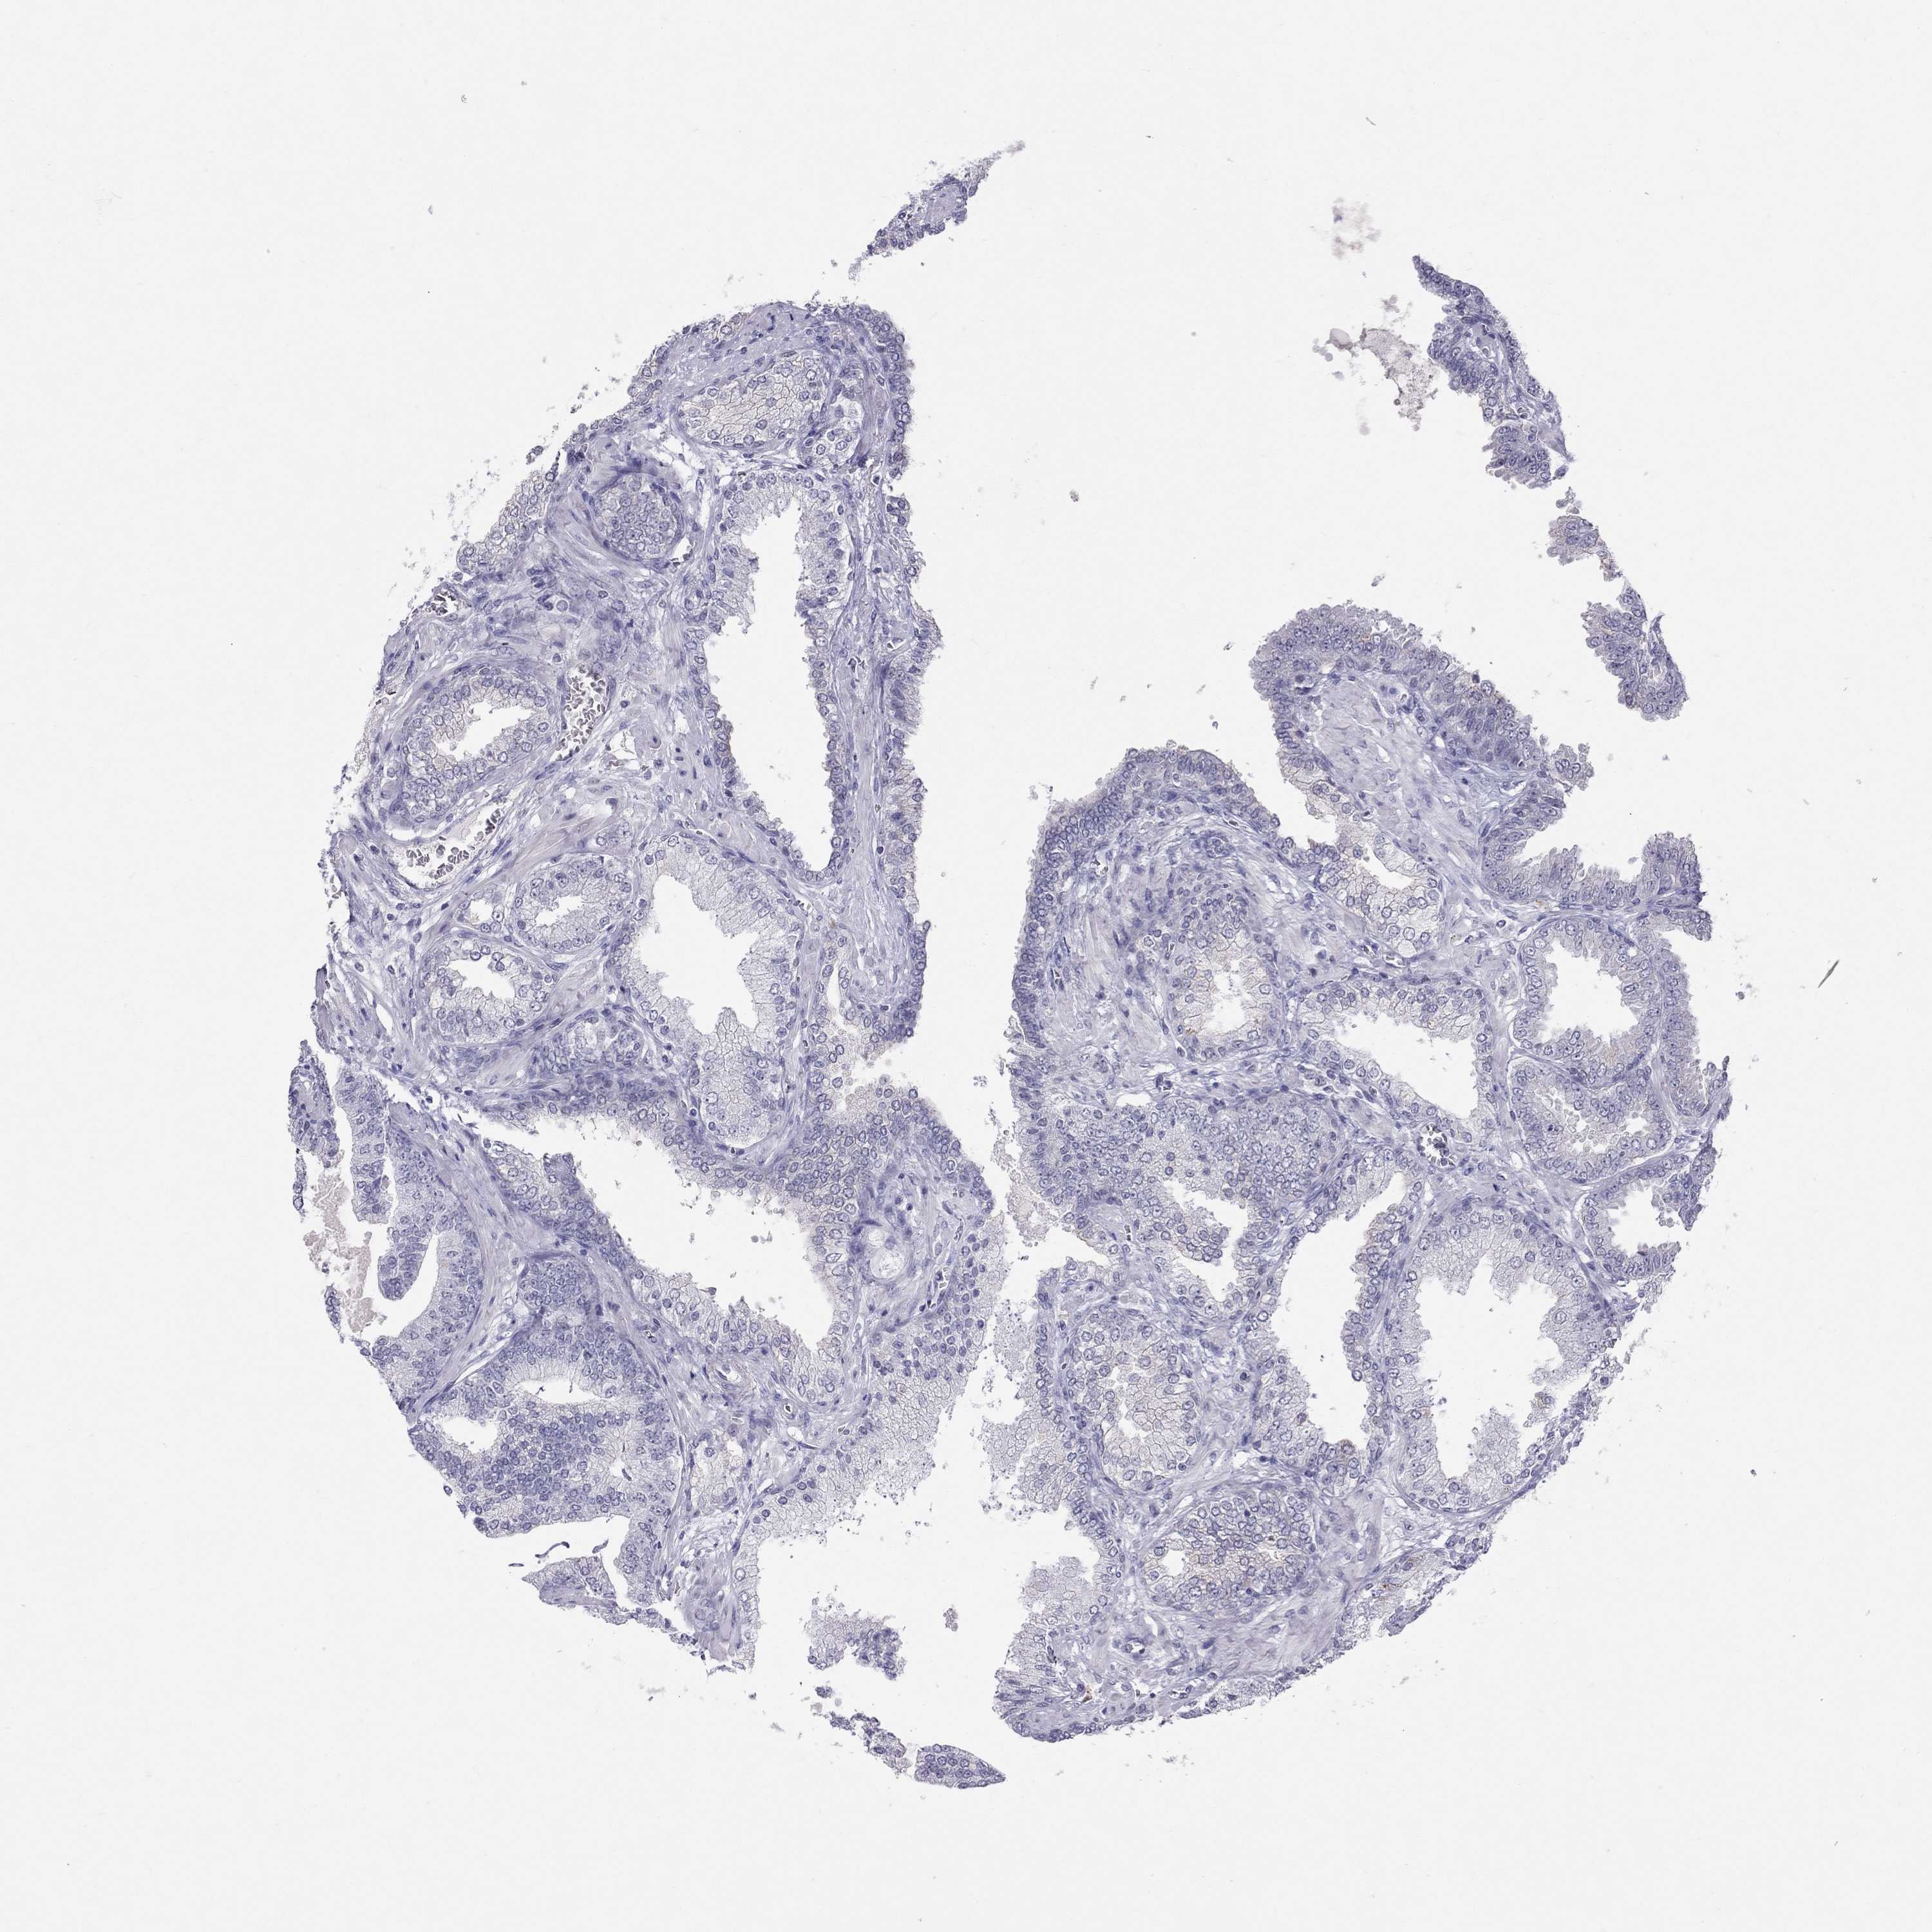

PROSTATE CANCER - Protein expressioni

A mouse-over function shows sample information and annotation data. Click on an image to view it in a full screen mode. Samples can be filtered based on level of antibody staining by selecting one or several of the following categories: high, medium, low and not detected. The assay and annotation is described here.

Note that samples used for immunohistochemistry by the Human Protein Atlas do not correspond to samples in the TCGA dataset.

Antibody stainingi

Antibody staining in the annotated cell types in the current human tissue is reported as not detected, low, medium, or high, based on conventional immunohistochemistry profiling in selected tissues. This score is based on the combination of the staining intensity and fraction of stained cells.

Each image is clickable and will lead to virtual microscopy that enables deeper exploration of all samples and also displays staining intensity scores, fraction scores and subcellular localization as well as patient and tissue information for each sample.

Antibody HPA077658

Antibody HPA077748

Staining

High

Medium

Low

Not detected

Intensity

Strong

Moderate

Weak

Negative

Quantity

>75%

75%-25%

<25%

None

Location

Nuclear

Cytoplasmic/membranous

Cytoplasmic/membranous,nuclear

Adenocarcinoma, Medium grade

Adenocarcinoma, High grade

Adenocarcinoma, NOS

Adenocarcinoma, Low grade